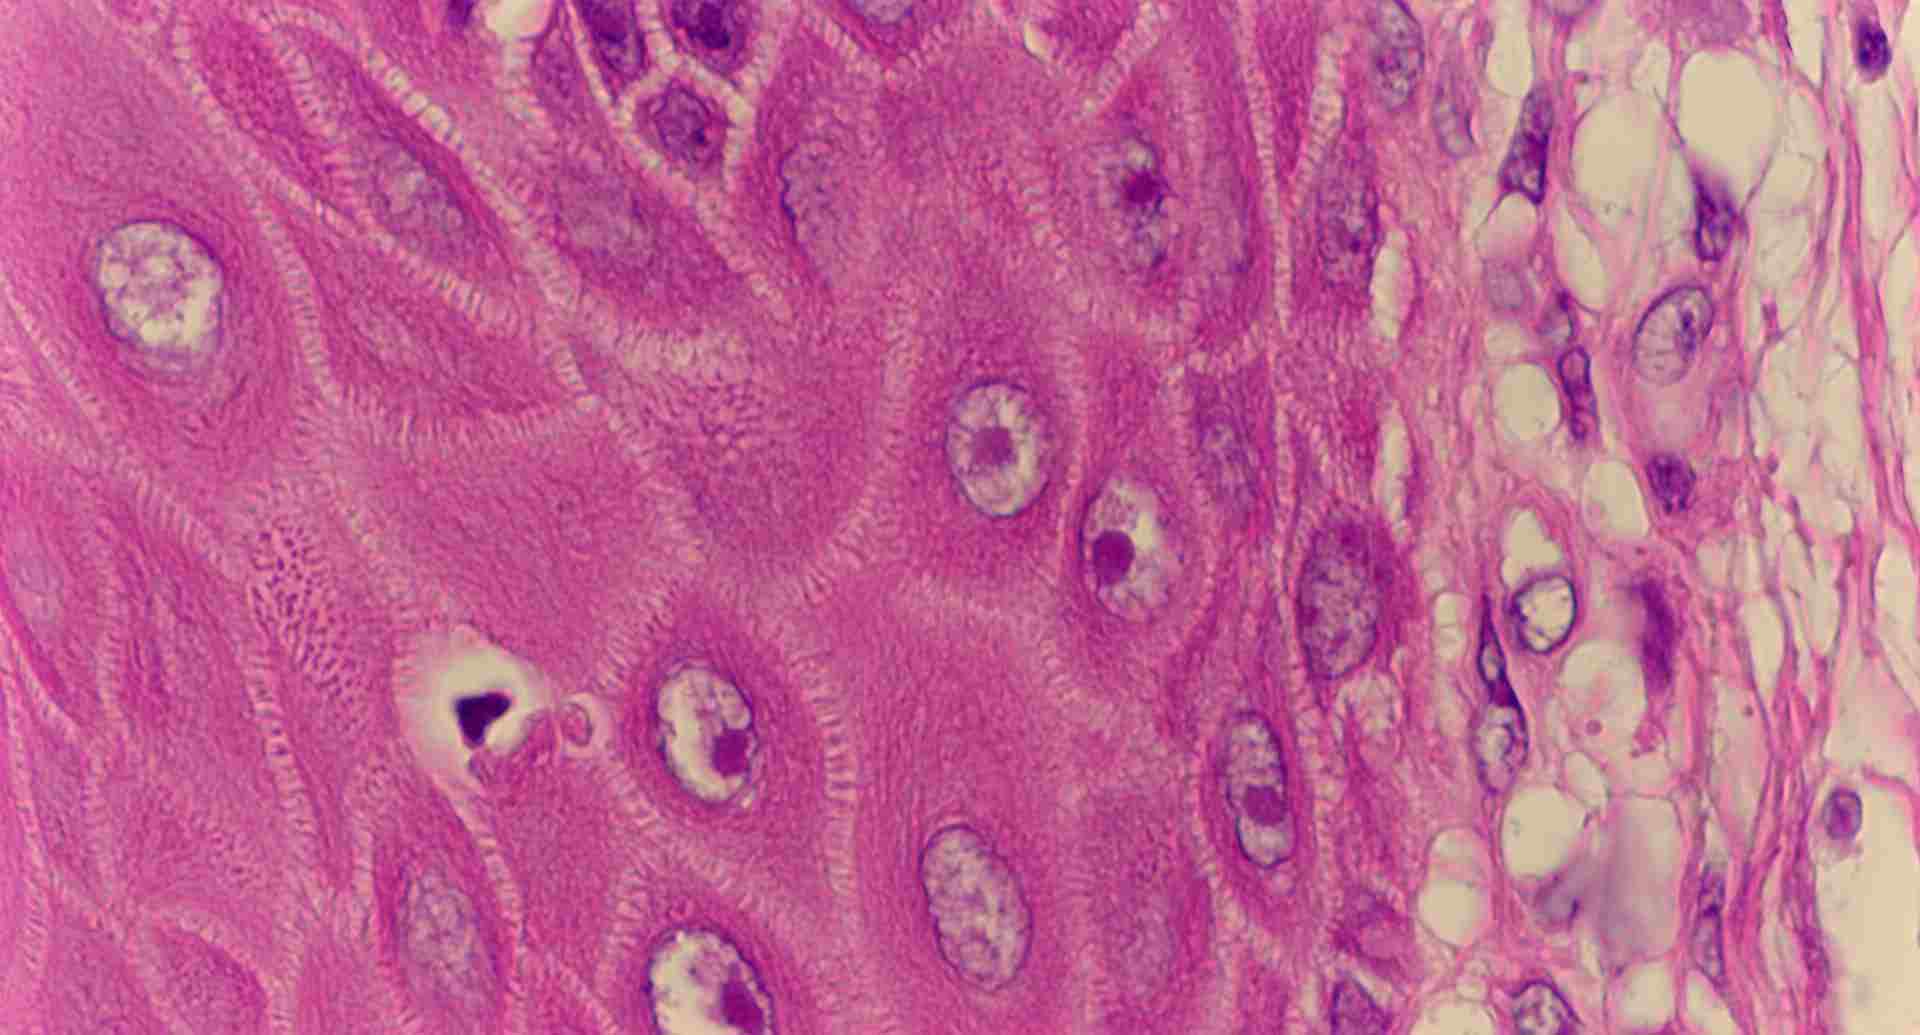

標本6